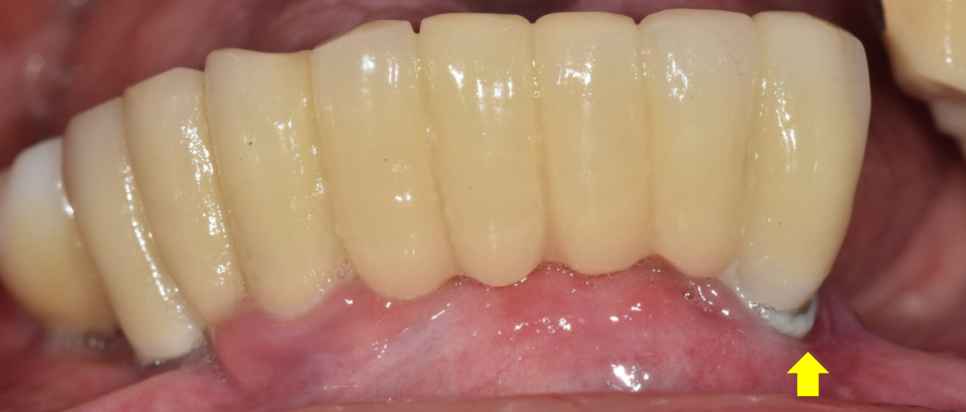

230116 고덕동치과

계속된 뼈 손실은 임플란트를 붙잡지 못하여

흔들거리게 되고

제거가 필요해질 수 있습니다.